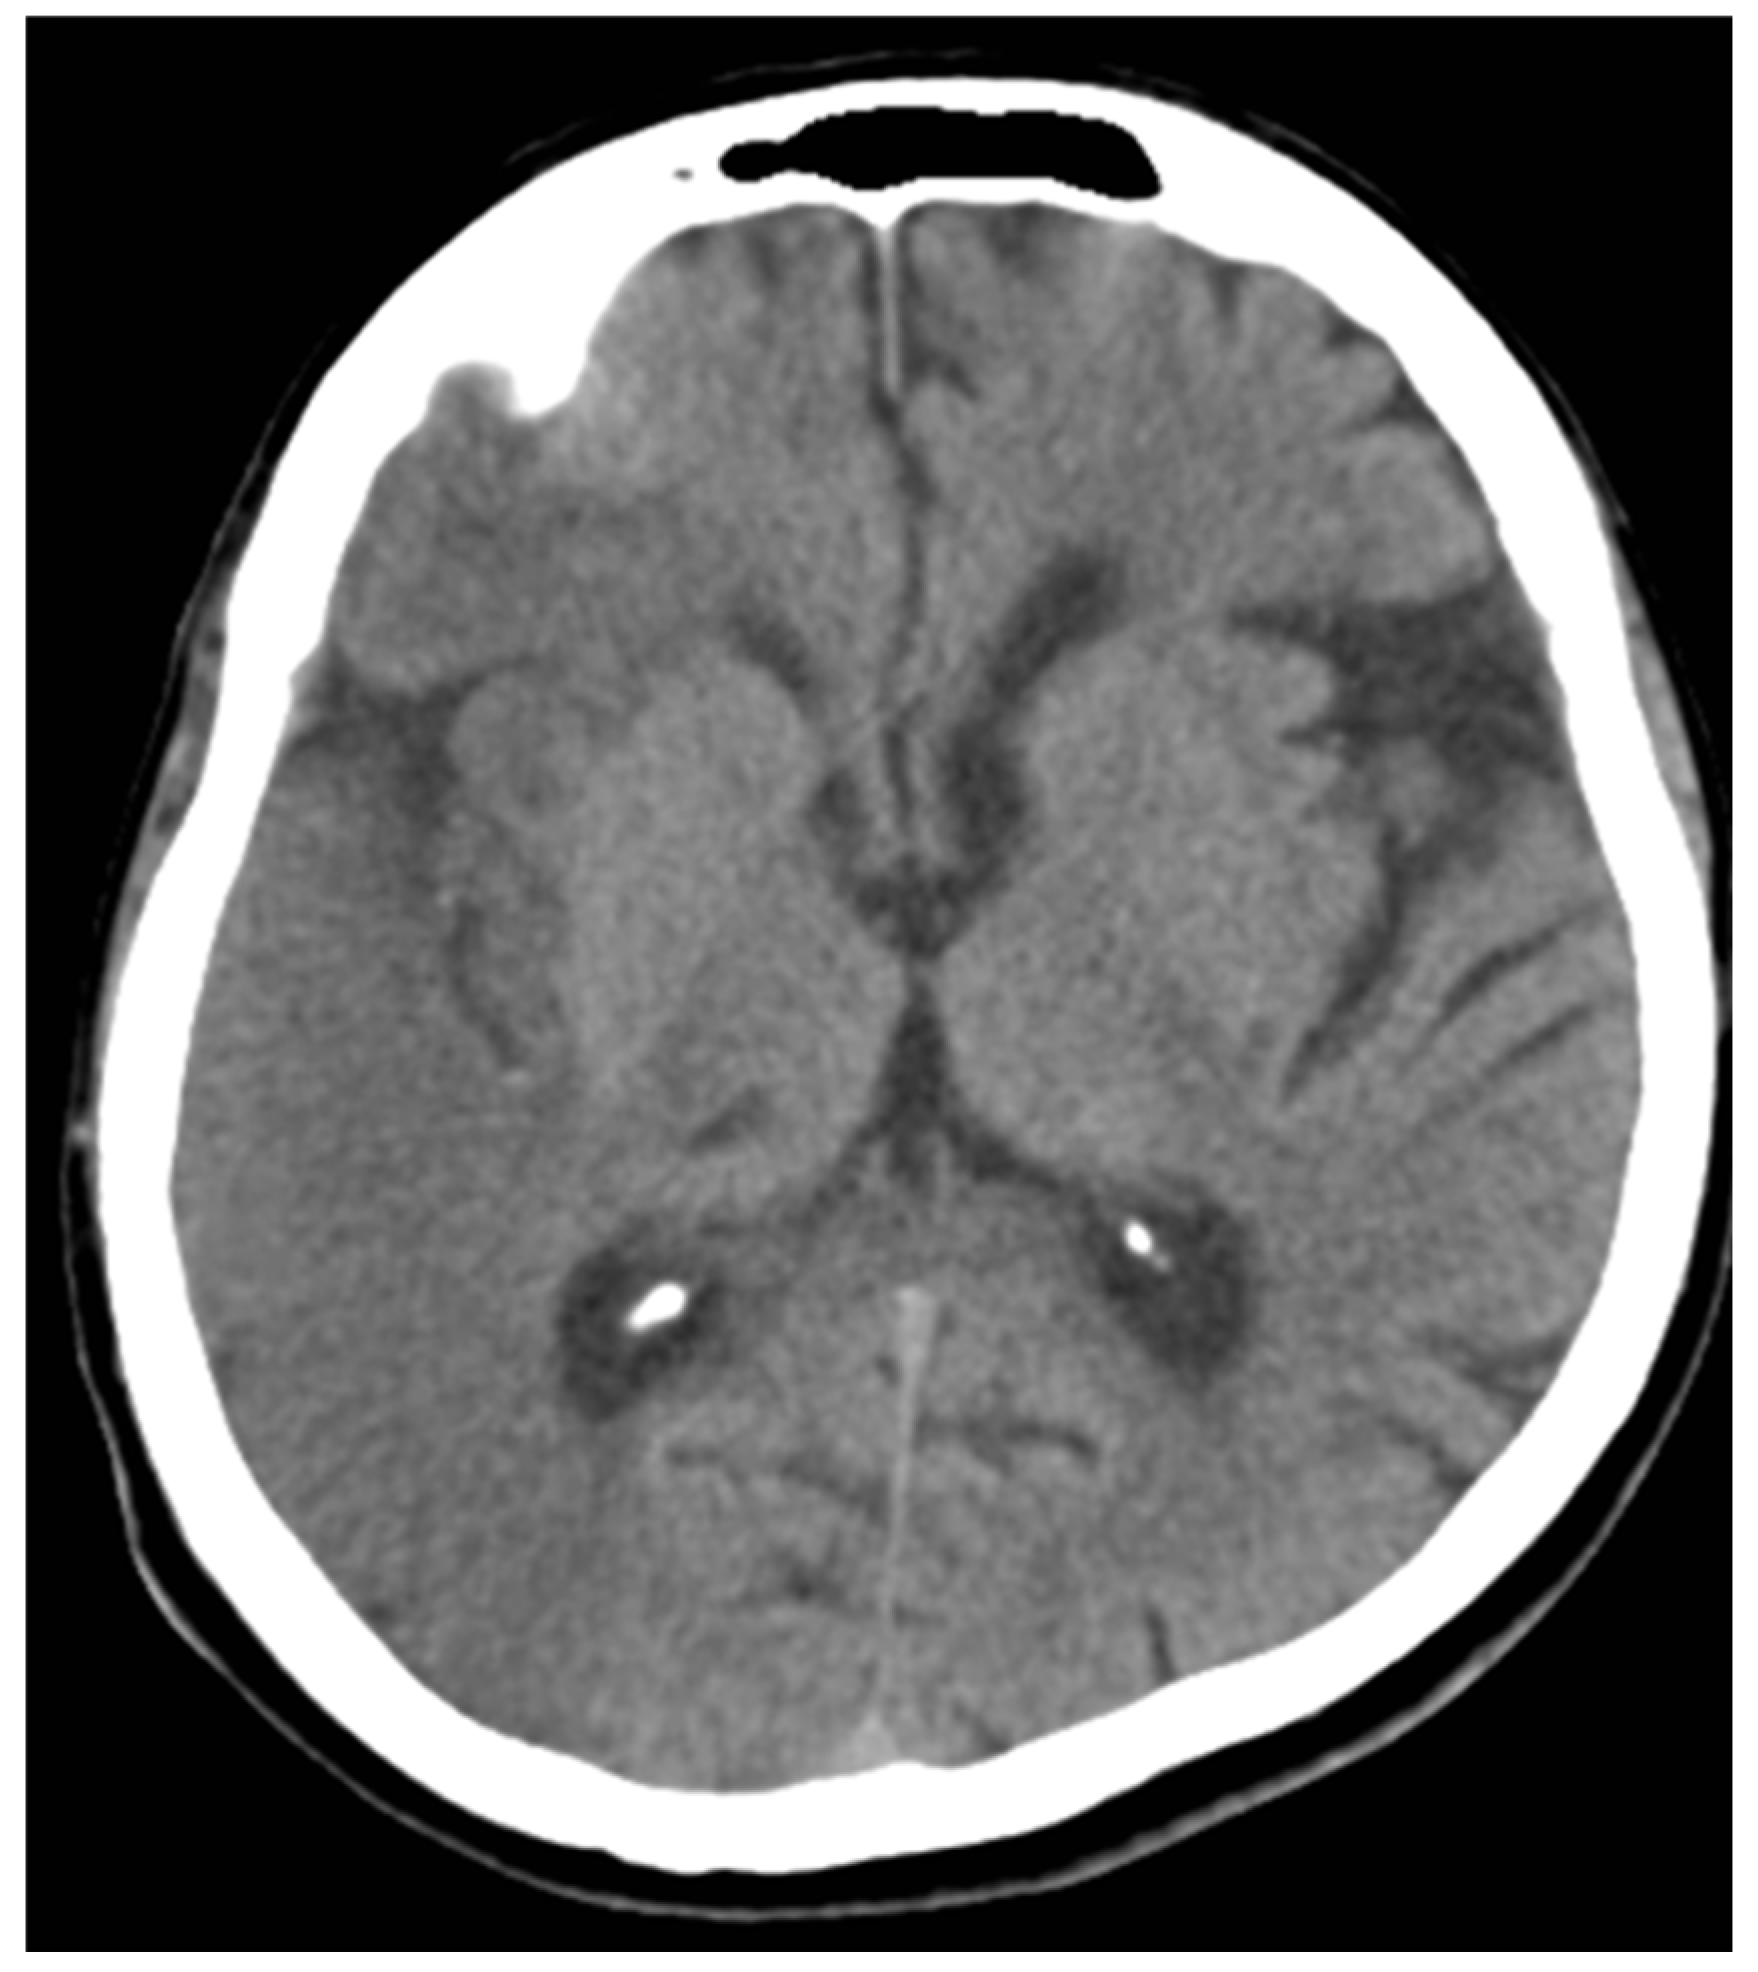

Case 4: A 65-year-old man with diplopia and loss of balance for 3 days. CT shows an ill-defined hypodensity in the left half of the Pons region.

ANTERIOR MCA- 10, ASPECTS PCA-8

The patient showed a good prognosis during follow-up after 10 days.

Figure 4. NCCT of case 4.